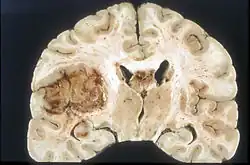

Examen macroscópico

A pesar de la corta duración de los síntomas, los glioblastomas suelen ser grandes en el momento de la presentación y pueden ocupar más de un lóbulo. La lesión es en general unilateral, aunque las del tronco cerebral y el cuerpo calloso pueden tener simetría bilateral. El tumor ocupa la misma posición en los dos hemisferios y muestra un aspecto de "mariposa". La extensión supratentorial bilateral se debe a un rápido crecimiento a lo largo de las estructuras mielinizadas, en particular a través del cuerpo calloso y a lo largo del fórnix hacia los lóbulos temporales. Los límites de la masa neoplásica, que no está encapsulada, son difusos por todas partes. La coloración es grisácea, pero pueden encontrarse abundantes variaciones de color, causadas por necrosis o hemorragias más o menos recientes, por lo que sobre el fondo gris aparecen zonas amarillentas, por degeneración grasa o necrosis y zonas de color rojizo o negruzco debidas a hemorragia.

La zona periférica del tejido tumoral hipercelular aparece como un borde suave y gris. El tejido necrótico puede bordear estructuras cerebrales adyacentes sin una zona tumoral intermedia detectable macroscópicamente. La necrosis central puede ocupar más del 80 % de la masa total del tumor.

Los glioblastomas están generalmente salpicados de manchas rojas y marrones debidas al sangrado. A veces son lo suficientemente grandes como para causar síntomas similares a un accidente cerebrovascular, que puede ser el primer signo clínico del tumor. Los quistes macroscópicos, cuando están presentes, contienen un fluido turbio proveniente del tejido tumoral necrótico licuado, en claro contraste con los quistes de retención bien definidos de los astrocitomas difusos de grado II.

La mayoría de los glioblastomas de los hemisferios cerebrales son claramente intraparenquimatosos, con epicentro en la materia blanca. A veces la neoplasia se presenta como ampliamente superficial y en contacto con leptomeninge y duramadre, y se puede confundir con un carcinoma metastásico o con una lesión extra-axial, como el meningioma.[11][61]